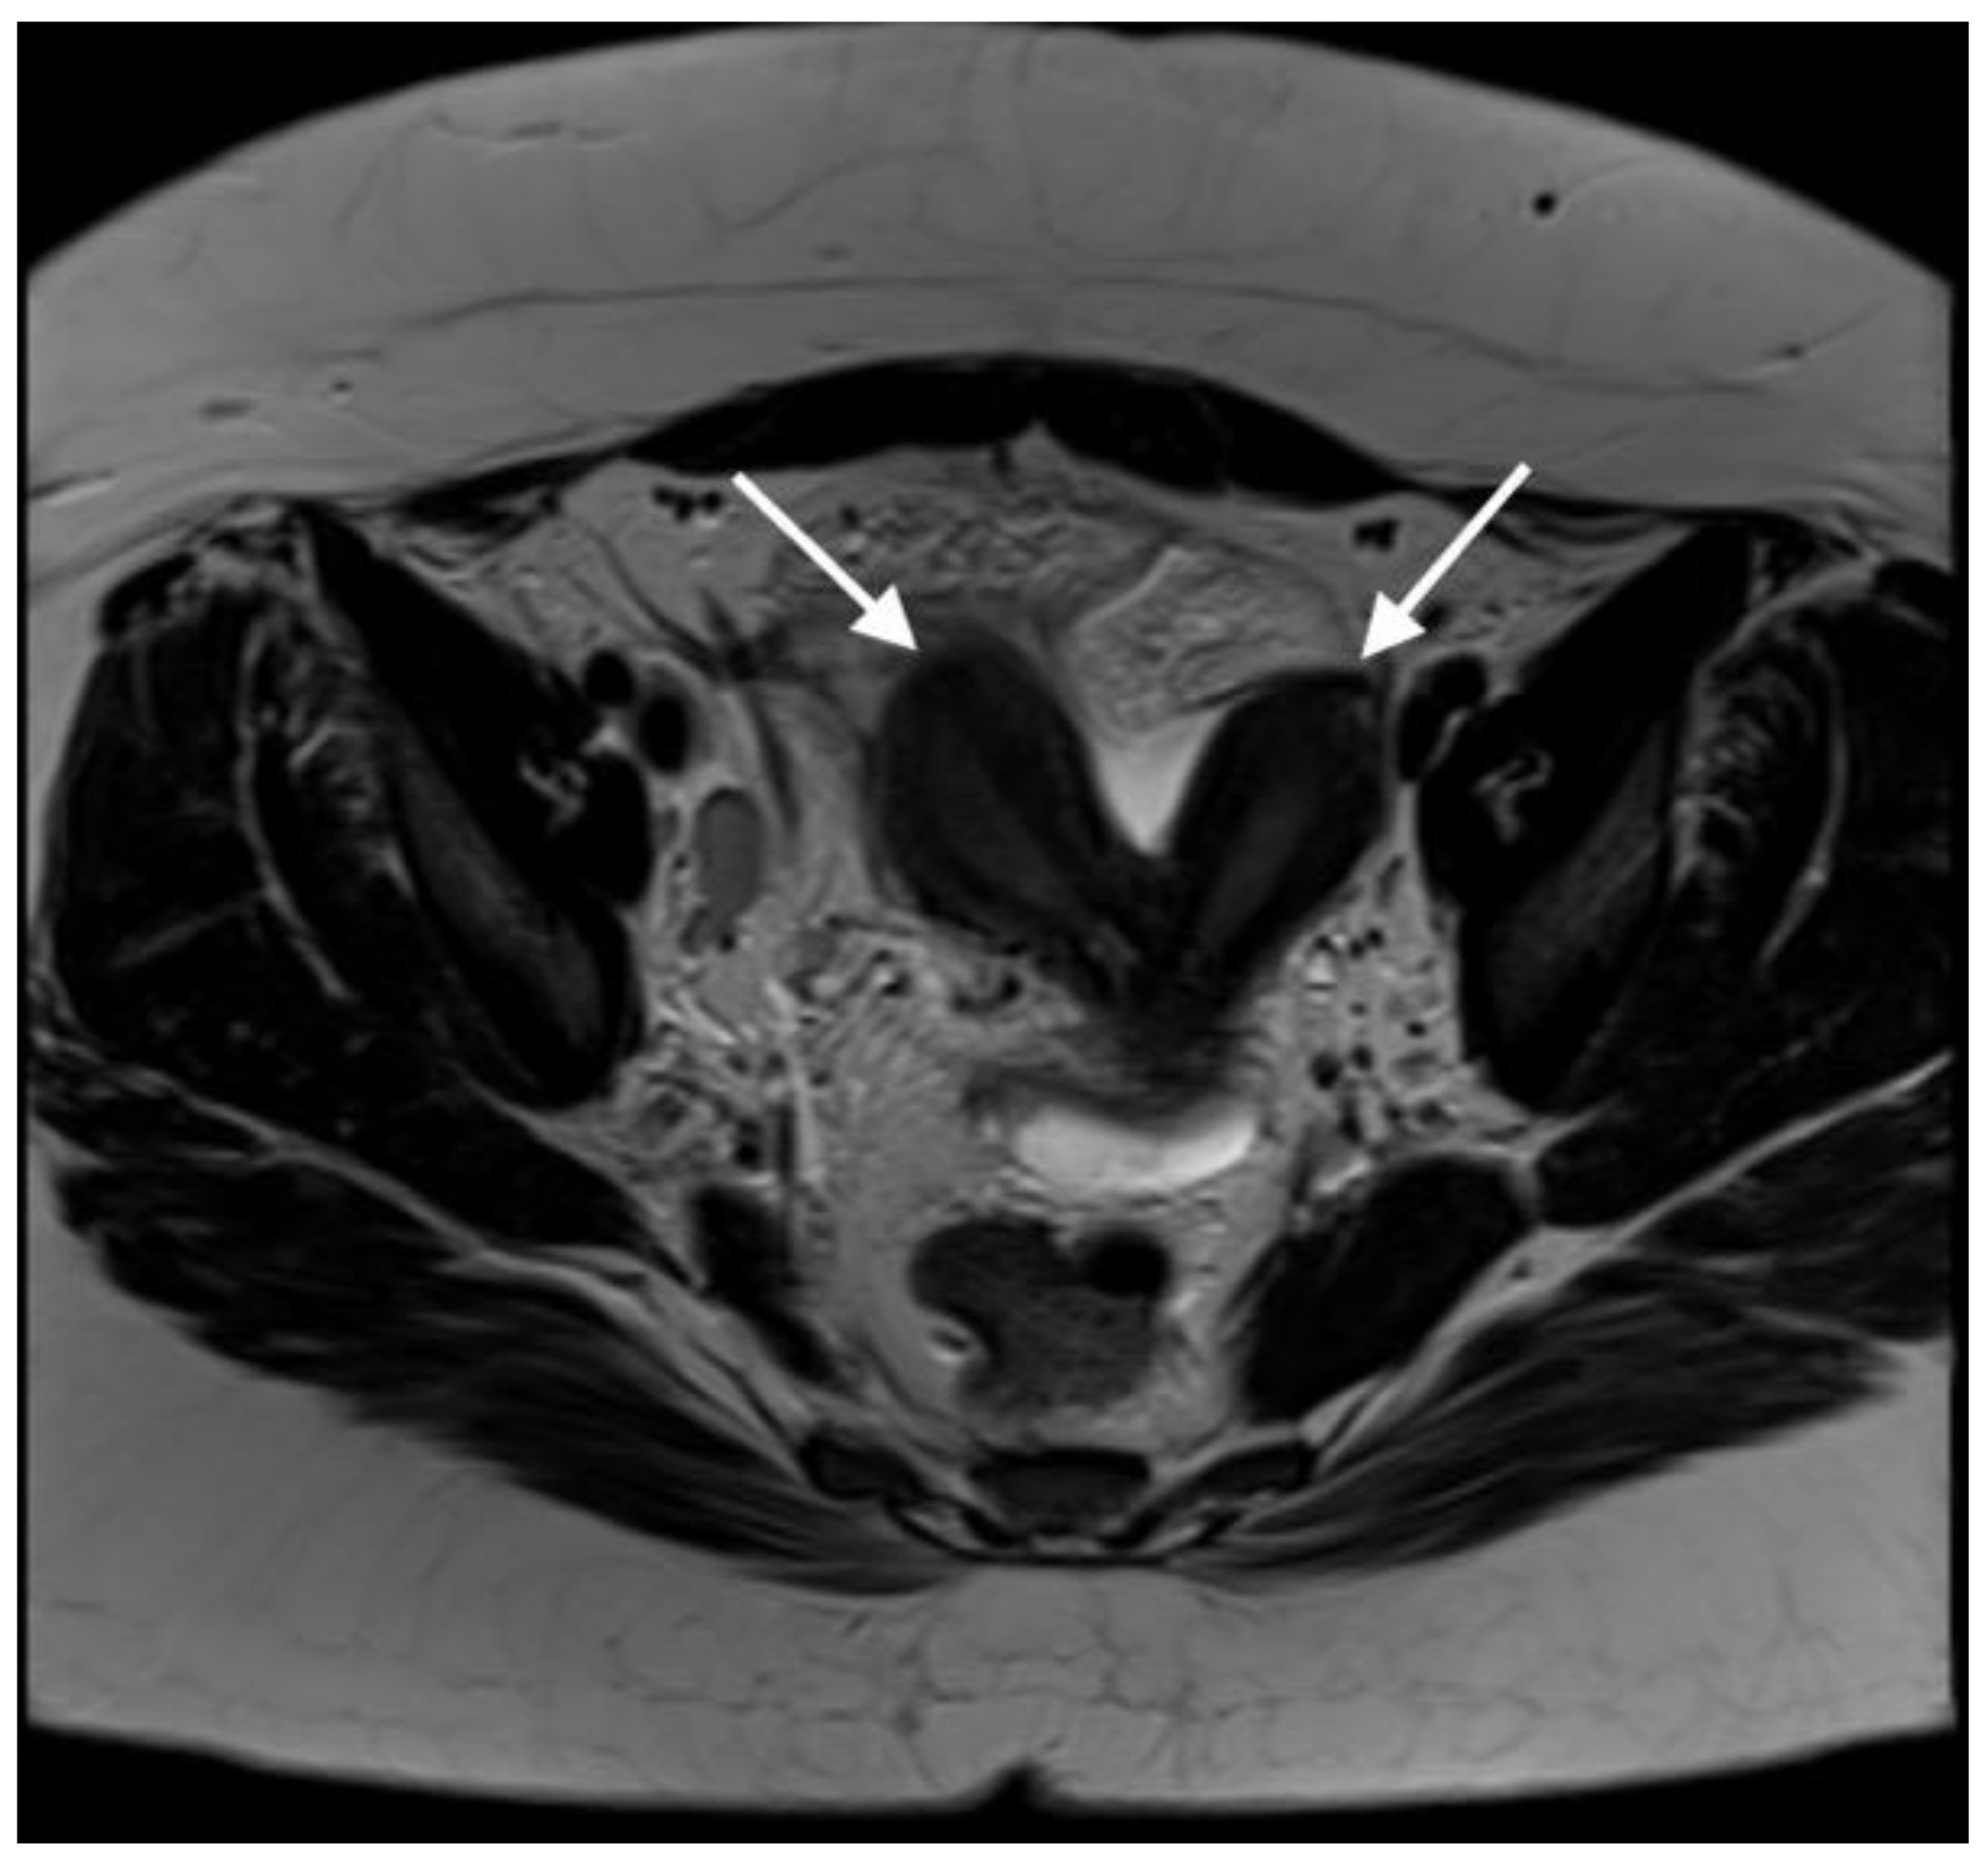

Axial T2-weighted MR image demonstrates uterus didelphys (two uterine cavities indicated by white arrows). A 21-year-old woman presented with lower abdominal and back pain, mainly located on the right side. The pain was constant and progressively worsened over a six-day period. She also reported episodes of vomiting over the last two days, constipation and a loss of appetite. Additionally, she had a previous assessment in A + E five days prior to this admission, where she was diagnosed with a chest infection and was treated with Co-amoxiclav. Her previous medical history and family history were unremarkable, she had never had any previous surgeries, had never conceived and was not allergic to any medication. Initially, she was assessed by members of the A + E team and was referred to the surgical team to exclude appendicitis or mesenteric adenitis. Upon examination, her abdomen was soft with voluntary guarding on the right iliac fossa. She was pyrexial (T: 38.1 °C), tachycardic (HR: 129 bpm), tachypnoeic (RR: 19), with normal blood pressure (BP: 119/80 mmHg) and oxygen saturation levels (SO2: 98%). Biochemical and haematological investigations revealed elevated CRP (>320 mg/L), white cell count (WCC: 16 × 109/L) and platelets levels (405 × 109/L). The liver and kidney functions were normal. Venous blood gas indicated a pH of 7.35 and lactate levels of 1.3 mmol/L. The urine sample indicated the presence of leucocytes, protein and blood. The urine pregnancy test was negative. The patient underwent a CT of her abdomen/pelvis after the initial surgical review. It revealed a large complex pelvic collection, measuring 7 × 6 × 10 cm, arising from the right adnexa, with the inflammatory process extending into the uterus. The CT also suggested incidental right renal agenesis, which the patient was not aware of. The findings were suggestive of a tubo-ovarian abscess (TOA), and the patient was started on intravenous ceftriaxone and metronidazole, as per the unit’s protocol. Due to the CT scan findings, the patient was then referred to the gynaecology team. Her gynaecological history indicated a menarche at 10 years of age. Her periods were regular, but she reported significant dysmenorrhea and heavy menstrual bleeding. Clinical examination including a speculum exam revealed that the cervix was difficult to visualise, since it was deviated to the left. A purulent foul-smelling discharge was also noted as well as a fullness on the anterior fornix, but no signs of significant tenderness were present at the time of the examination. After the gynaecological assessment, a pelvic ultrasound was requested to further characterize the pelvic mass. TVUSS was performed approximately 24 h after the CT, while the patient remained febrile. The sonographic assessment revealed the collection, previously attributed to the TOA, but the additional finding of uterus didelphys with two cervices was also noted. The combination of renal agenesis and uterine abnormality raised the possibility of a Müllerian abnormality; thus, an abdomen/pelvis MRI with contrast was requested in order to confirm the diagnosis. The MRI report confirmed that there was a double uterus and cervix and further added that there was a longitudinal vaginal septum (U3bC2V2 based on the ESHRE/ESGE classification [1]).